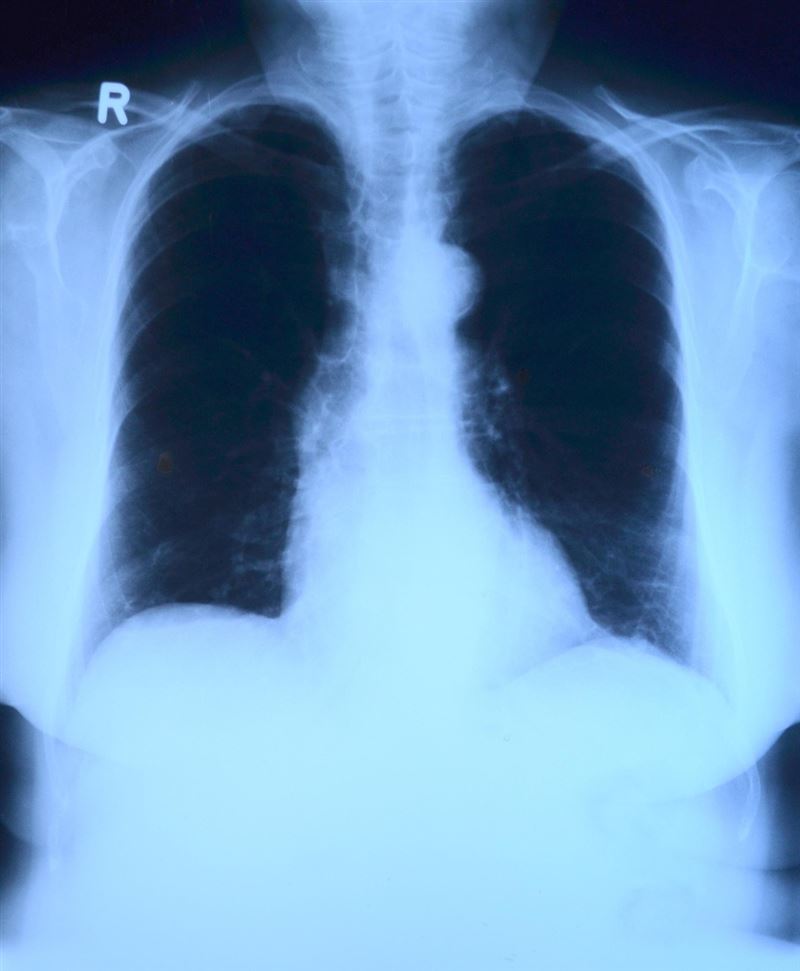

不過,王韋力替孩子聽診時,立即察覺不對勁。雖然孩子活動力尚可,但聽診器傳來的呼吸聲非常奇怪,一側肺部有水聲,另一側甚至幾乎聽不到呼吸音。他當機立斷,建議媽媽帶孩子照X光,懷疑是嚴重肺炎,可能合併積水需要住院治療。

結果一檢查,發現孩童「左邊的肺部整個都白掉了!」王韋力強調,這是嚴重的肺部積水表現,孩子一度面臨插胸管引流和轉入加護病房的風險。幸好,透過及時的物理治療和抗生素療程,孩子最終康復。